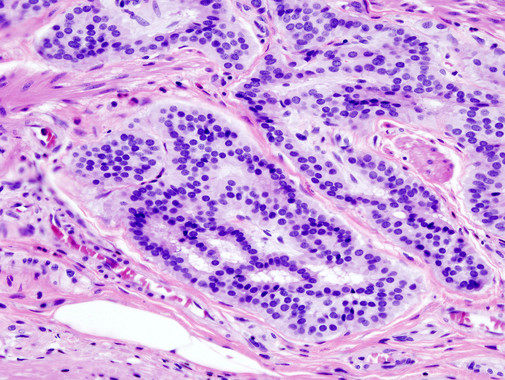

Investigadores españoles han elaborado un sistema que clasifica, en el momento del diagnóstico, a los pacientes de cáncer colorrectal en tres grupos con diferente riesgo de recaída. Para ello, analizaron la mutación del gen BRAF en 87 casos y combinaron esta información con un sistema de estadificación que evalúa la extensión y el grado de infiltración del tumor. El resultado, publicado en la revista Oncotarget, hace posible discriminar tres tipos de pacientes con distinto riesgo de recaída, lo que permitiría realizar un seguimiento más estrecho en los pacientes de alto riesgo.

Investigadores españoles han elaborado un sistema que clasifica, en el momento del diagnóstico, a los pacientes de cáncer colorrectal en tres grupos con diferente riesgo de recaída. Para ello, analizaron la mutación del gen BRAF en 87 casos y combinaron esta información con un sistema de estadificación que evalúa la extensión y el grado de infiltración del tumor. El resultado, publicado en la revista Oncotarget, hace posible discriminar tres tipos de pacientes con distinto riesgo de recaída, lo que permitiría realizar un seguimiento más estrecho en los pacientes de alto riesgo.

“En el cáncer colorrectal la mayoría de las muertes se producen por metástasis o por recaídas”, explica José María Sayagués, investigador del Hospital Clínico Universitario de Salamanca y del Instituto de Investigación Biomédica de Salamanca (IBSAL). “Generalmente, si el tumor se detecta en fases tempranas basta con una intervención quirúrgica, pero incluso en este caso hay cerca de un 10% de pacientes que recaen o desarrollan metástasis y no tenemos ningún biomarcador para identificarlos”, afirma.

Por eso, los servicios de Anatomía Patológica, Hematología y Cirugía centraron su atención en el estudio de una serie de genes de relevancia desde el punto de vista de su implicación en el desarrollo de la enfermedad, la respuesta al tratamiento y la supervivencia de los pacientes.

Sin embargo, la investigación no se limita a señalar la importancia de este biomarcador. Los expertos han elaborado un método de puntuación que combina dos parámetros. El primero de ellos es el sistema de estadificación del cáncer colorrectal, que considera el grado de infiltración del tumor en la pared del intestino y su diseminación en tejidos cercanos, ganglios linfáticos y metástasis en otros órganos. El segundo incorpora la información sobre la presencia o ausencia de mutaciones sobre el gen BRAF.